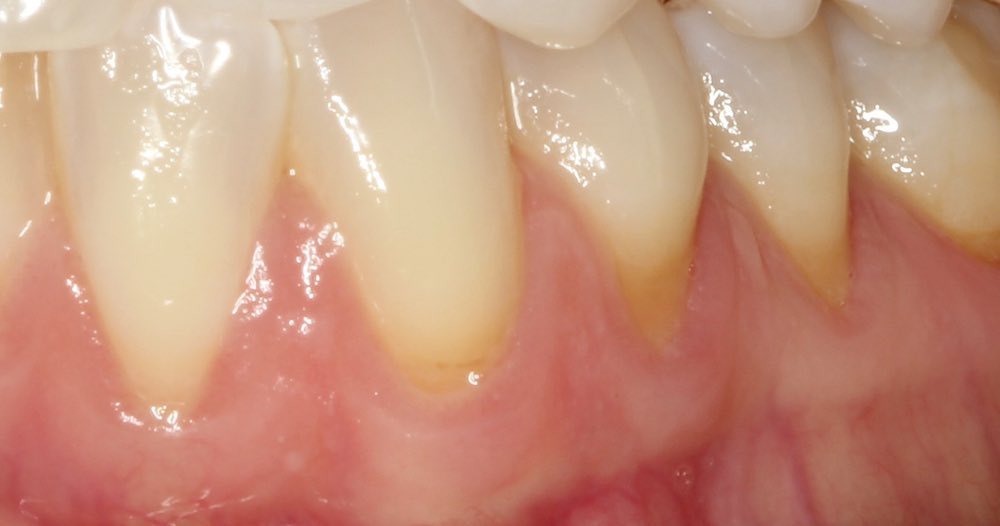

Connective Tissue Gingival Grafting for Gingival Recession